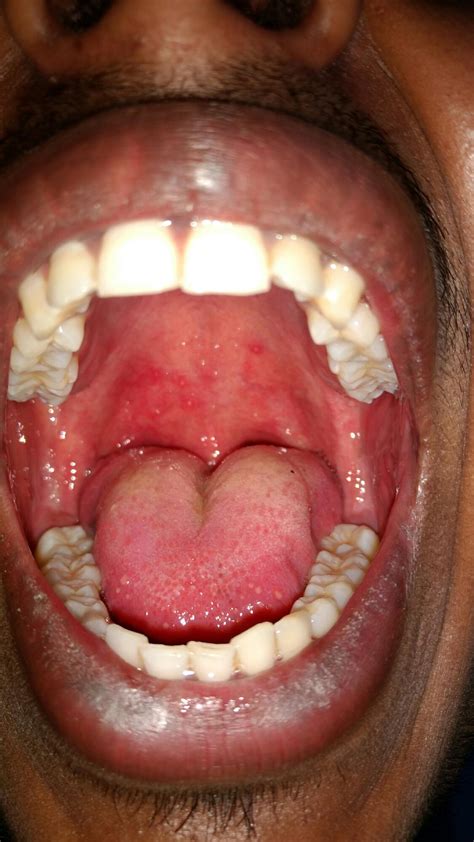

Ulcers in the throat, also known as throat ulcers or aphthous ulcers, are a common condition that can cause significant discomfort and pain. These ulcers are typically small, round, or oval-shaped sores that develop on the mucous membranes of the throat. They can vary in size and number, and while they are usually not serious, they can be quite bothersome. Understanding the causes, symptoms, and treatment options for ulcers in the throat is essential for managing this condition effectively.

Symptoms of Ulcers in Throat

The symptoms of ulcers in the throat can vary depending on the underlying cause and the severity of the condition. Common symptoms include:

• Pain and Discomfort: Ulcers in the throat can cause significant pain, especially when swallowing or talking.

• Redness and Swelling: The affected area may appear red and swollen.

• White or Yellow Coating: Some ulcers may have a white or yellow coating.

• pictures of ulcers in throat